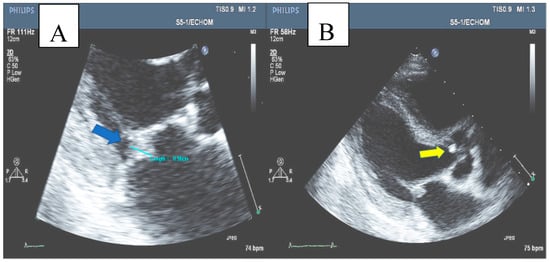

A trans-thoracic echocardiogram (TTE) revealed normal left ventricular (LV) and right ventricular (RV) function, moderate mitral regurgitation, and a 0.9 × 0.8 cm mobile mass in the atrial aspect of the posterolateral leaflet of the mitral valve, as well as a small mass on the aortic valve with normal function of the valve, consistent with vegetation on both valves. Trans-esophageal echocardiogram revealed the same findings (Figure 2). The diagnosis of infective endocarditis of the mitral and aortic valve was established.

Figure 2.

(A) Mitral valve vegetation (blue arrow). (B) Aortic valve vegetation (yellow arrow).